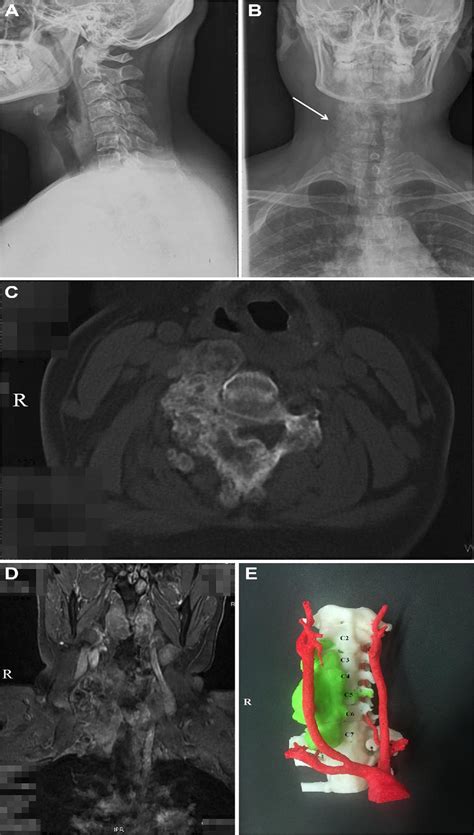

7,064 Cervical Vertebral Anatomy Images, Stock Photos & Vectors ...